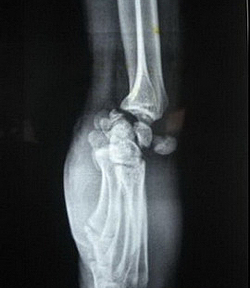

(Слева) На заднепередней рентгенограмме определяется оскольчатый внутрисуставной перелом основания первой пястной кости. Этот перелом Роландо возникает в результате осевого давления при частично согнутом большом пальце. Данный пациент 31 года получил травму при ударе кулаком.

(Справа) На заднепередней рентгенограмме виден внесуставной эпибазальный перелом первой пястной кости. Имеется локтевое угловое отклонение, поскольку два отломка смещаются в разных направлениях под действием местных сухожилий. (Слева) На заднепередней рентгенограмме определяется перелом Салтера-Харриса II типа ростковой пластинки первой пястной кости без смещения. Этот перелом произошел в результате лыжной травмы с переходом перелома через зону роста от медиального к латеральному краю, открываясь на метафизе.